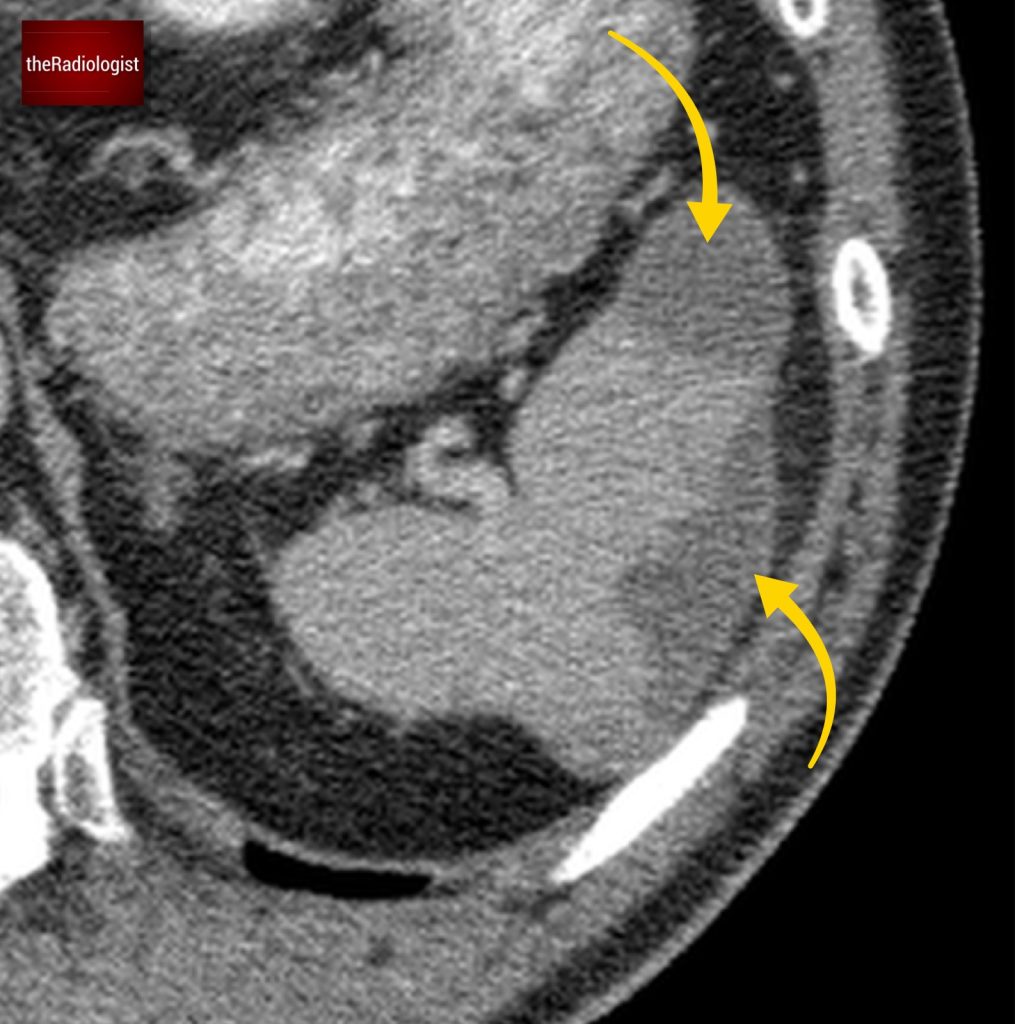

Also as we scroll down we can see there is fat stranding surrounding the psoas muscle extending into the pelvis.

There is fat stranding surrounding the psoas extending into the pelvis.